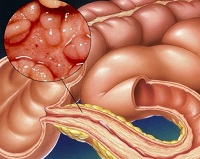

Súlyos visszatérő patológia „colitis ulcerosa” a gyermekek és felnőttek okoz fájdalmas tüneteket társított gyulladásos válasz a vastagbélben.

Nagy jelentősége van a megnyilvánulása a betegség állapotától bélnyálkahártyán. Amennyiben sérült vagy genetikailag kialakult sérülékeny, gyulladás és bakteriális fertőzés átterjed az összes réteget a bél, és ő már nem képes a regenerálódásra.

Nekrotizáló bélkárosodást, inherens colitis, ami a veszélyes szövődmények - tágulása a vastagbél toxémia. Súlyos gyulladásos támadás provokál egy speciális szegmens vagy egy teljes bél, ahol a késleltetett széklet.

Villámgyors fejlesztés a nem-specifikus bélbetegség bonyolult néha perforáció a vastagbél, amely gyakran ad a halál okát. Gyulladásos nekrózisa a bélfalon elvékonyodik úgy, hogy sebezhetővé válik a toxinok a béltartalom. A perforációk is hozzájárul a baktériumok terjedését - az E. coli.